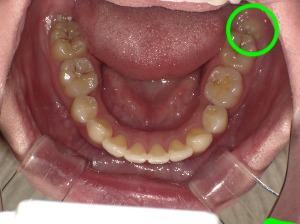

親知らずとは、奥歯の一番後ろに生えてくる第三大臼歯のことです。

現代人は顎が小さい傾向があるため、親知らずが斜めに生えたり、歯ぐきの中に埋まったままになったりすることが少なくありません。

親知らずが斜めに生えていると、手前の歯を押してしまい、歯並びが乱れる原因になることがあります。

横向きや斜めに生えている親知らずは、手前の歯を押して歯並びに影響する可能性があります。